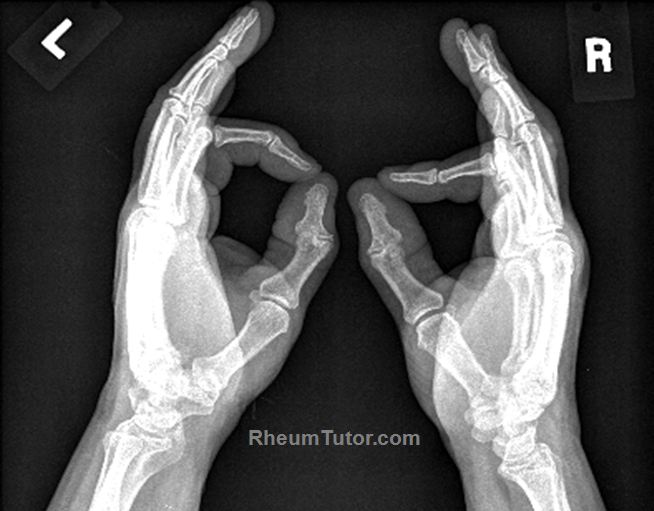

Your doctor can use them to diagnose or monitor problems with your hands, such as injuries,. Although additional radiographs can be taken. The hand series consists of posteroanterior, oblique, and lateral projections.